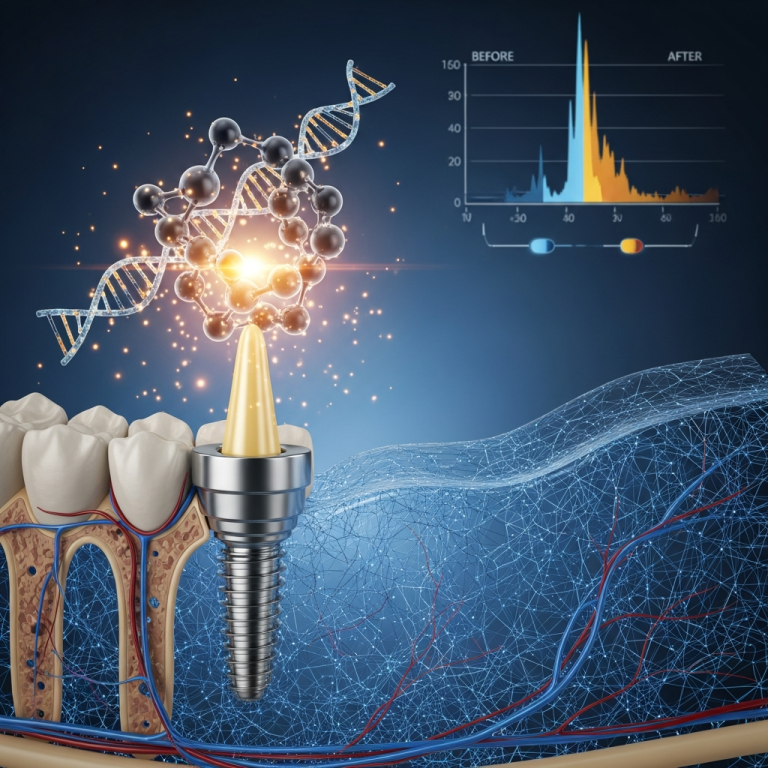

În implantologia dentară modernă, tehnica bicorticală monobloc aduce o paradigmă revoluționară, susținută de studii clinice recente (2025–2026). Aceasta permite încărcarea imediată, adică fixarea coroanei provizorii în același timp cu inserția implantului. Articolul de față prezintă dovezi obiective și avantajele exclusive ale acestei abordări, bazându-se pe date medicale actuale și pe mecanismul biomecanic superior oferit de ancorarea în ambele corticale osoase.

- Preservare osoasă: Distribuția forțelor pe ambele corticale minimizează resorbția osoasă crestală, conform unui studiu longitudinal din 2025.

Datele recente (2025–2026) confirmă că încărcarea imediată pe implanturi bicorticale monobloc este o procedură predictibilă atunci când este aplicată pe baza unor indicații stricte și a unei planificări avansate. Beneficiile biomecanice și de timp sunt semnificative, transformând abordarea în cazurile selective cu deficit osos.